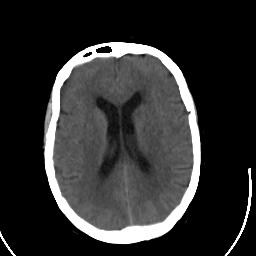

Stroke CT #2 -- Slice #15

[Home][Help][Clinical] Slice 15